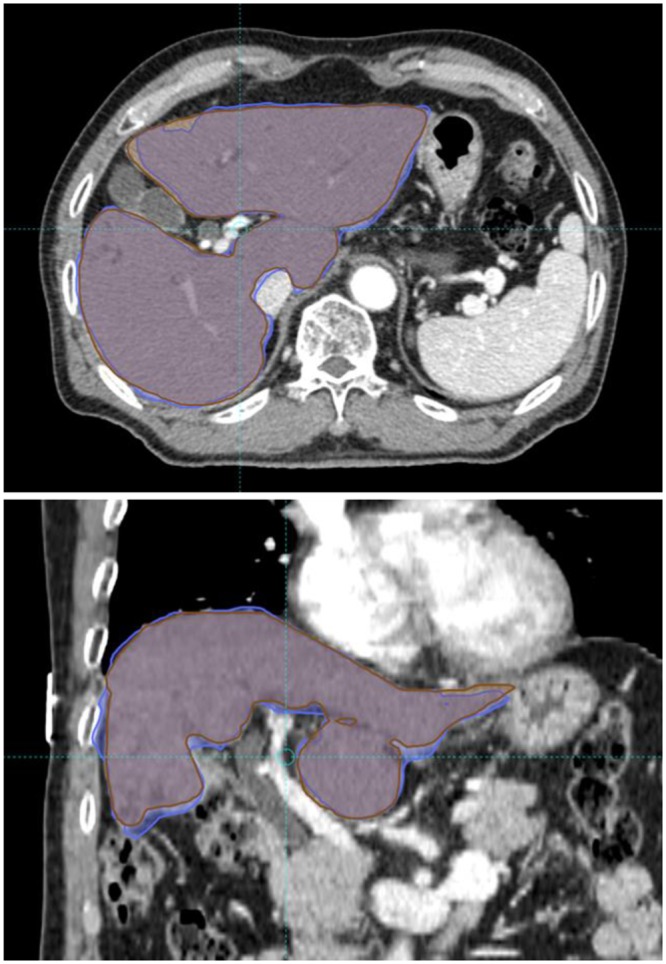

Deformable image registration and cumulative liver dose

DIR was performed in all patients, and an example DIR is presented in Fig. 1. Mean Dice similarity coefficient (DSC) index value was 0.93 with a standard deviation of 0.03. The DSC index value was >0.9 in 79 (92.9%) registrations, with a value < 0.85 in one registration. The DSC index of rigid registration (single transformation vector for all voxels) was always inferior to that of DIR. DSC indices of DIR and rigid registration are presented in Fig. 2.

Figure 1.

An example of deformable image registration. Liver contours were manually drawn on each computed tomography (CT) simulation image. The liver contour on the first CT simulation was deformed and registered onto the second CT image. The Dice similarity coefficient (DSC) was calculated between manually drawn liver contours in second CT simulation (brown) and the deformed contour from first CT simulation (blue). The DSC value of this patient was 0.94.